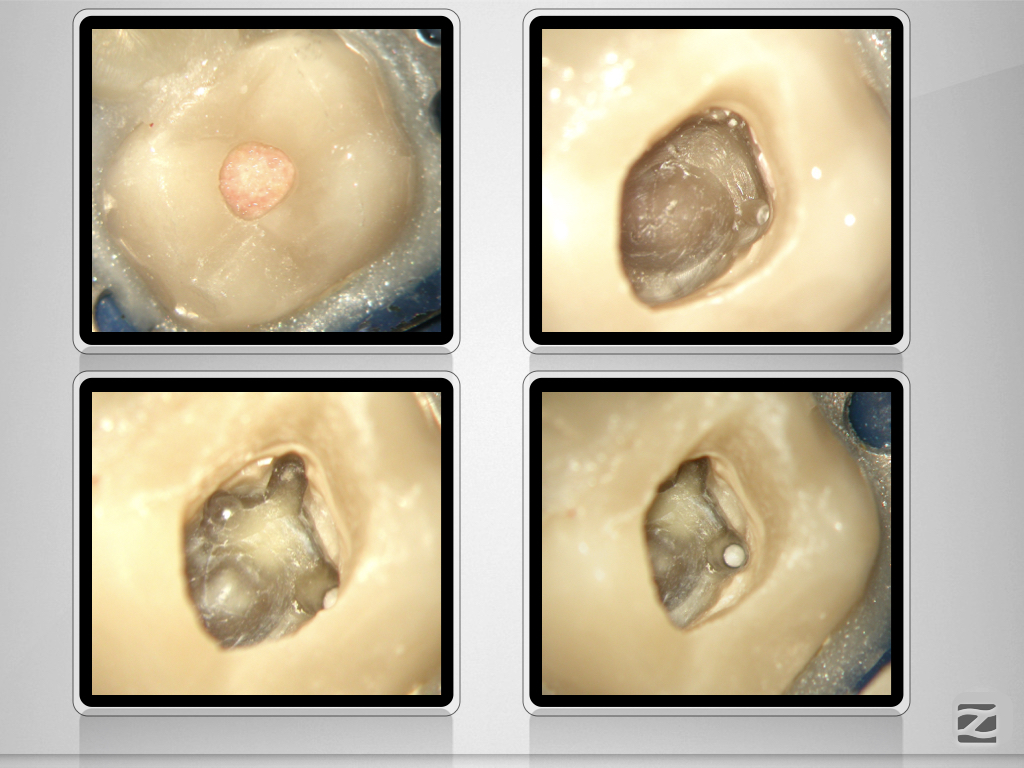

Wie hältst Du es mit dem Haarriss?